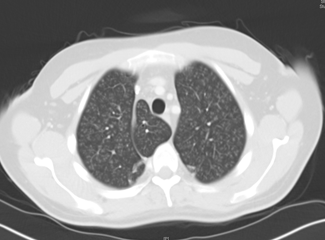

The patient's temperature was 101.5oF (38.6oC). Assessment of lung sounds found decreased air entry associated with bilateral rhonchi in upper and lower lung fields. Chest films showed bilateral perihilar markings suggestive of interstitial pneumonitis (Figure 1). The white blood cell (WBC) count was elevated (24,400/µL). Sputum was collected for culture, which later only showed WBCs, no organisms.